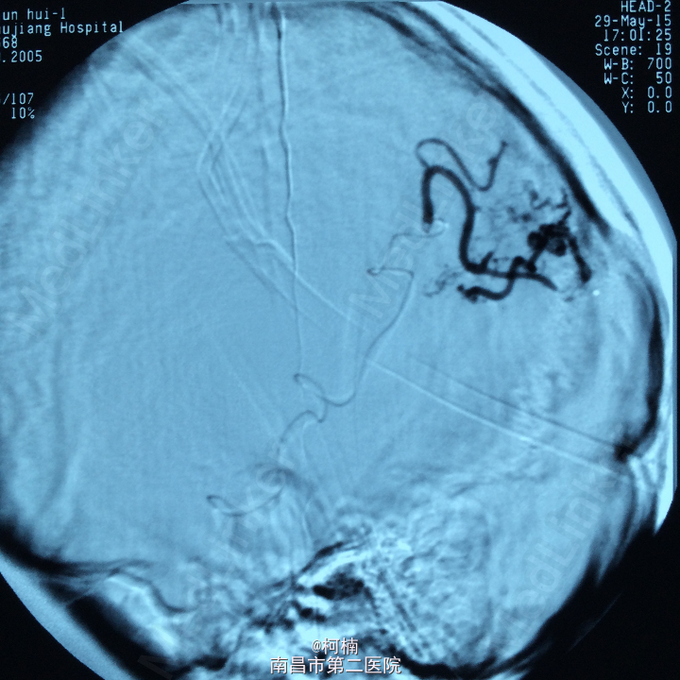

诊断:脑动静脉畸形 处理:予急诊行DSA检查,提示脑动静脉畸形,予行血管内栓栓塞治疗